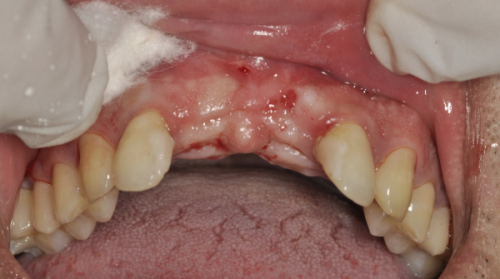

患者的颌骨条件也是影响种植牙多少钱一颗的重要因素。如果患者颌骨条件良好,骨量充足,那么在进行种植牙手术时就相对简单,不需要额外的处理,这种情况下,种植牙的价格可能在5000元 - 10000元一颗。然而,有些患者由于长期缺牙、牙槽骨吸收等原因,颌骨条件不足,在进行种植牙手术前,需要精良行骨移植或上颌窦提升术等额外的手术,以增加骨量,为种植牙提供良好的基础。这样一来,手术的难度和复杂度增加,费用也会相应提高,一般需要10000元 - 20000元一颗。